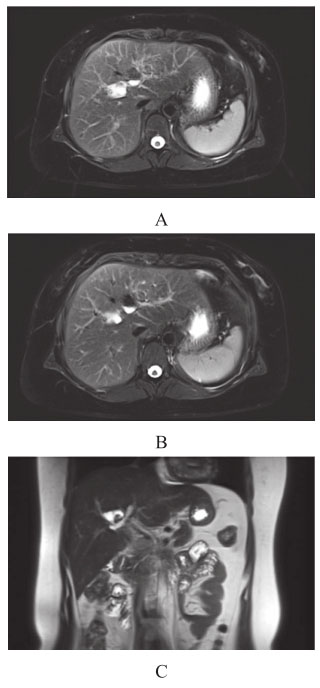

(6)磁共振胆胰管成像(MRCP)(2012年7月):左右肝管起始处扩张;右肝管可见结石;左肝内胆管略扩张(图2)。

图2 MRCP(2012年7月)

(7)MRCP(2018年1月):左右肝管起始部扩张积气;右肝管结石增大,直径约1.2cm;左肝内胆管略扩张;胆肠吻合口处结石(图3)。

图3 MRCP(2018年1月)